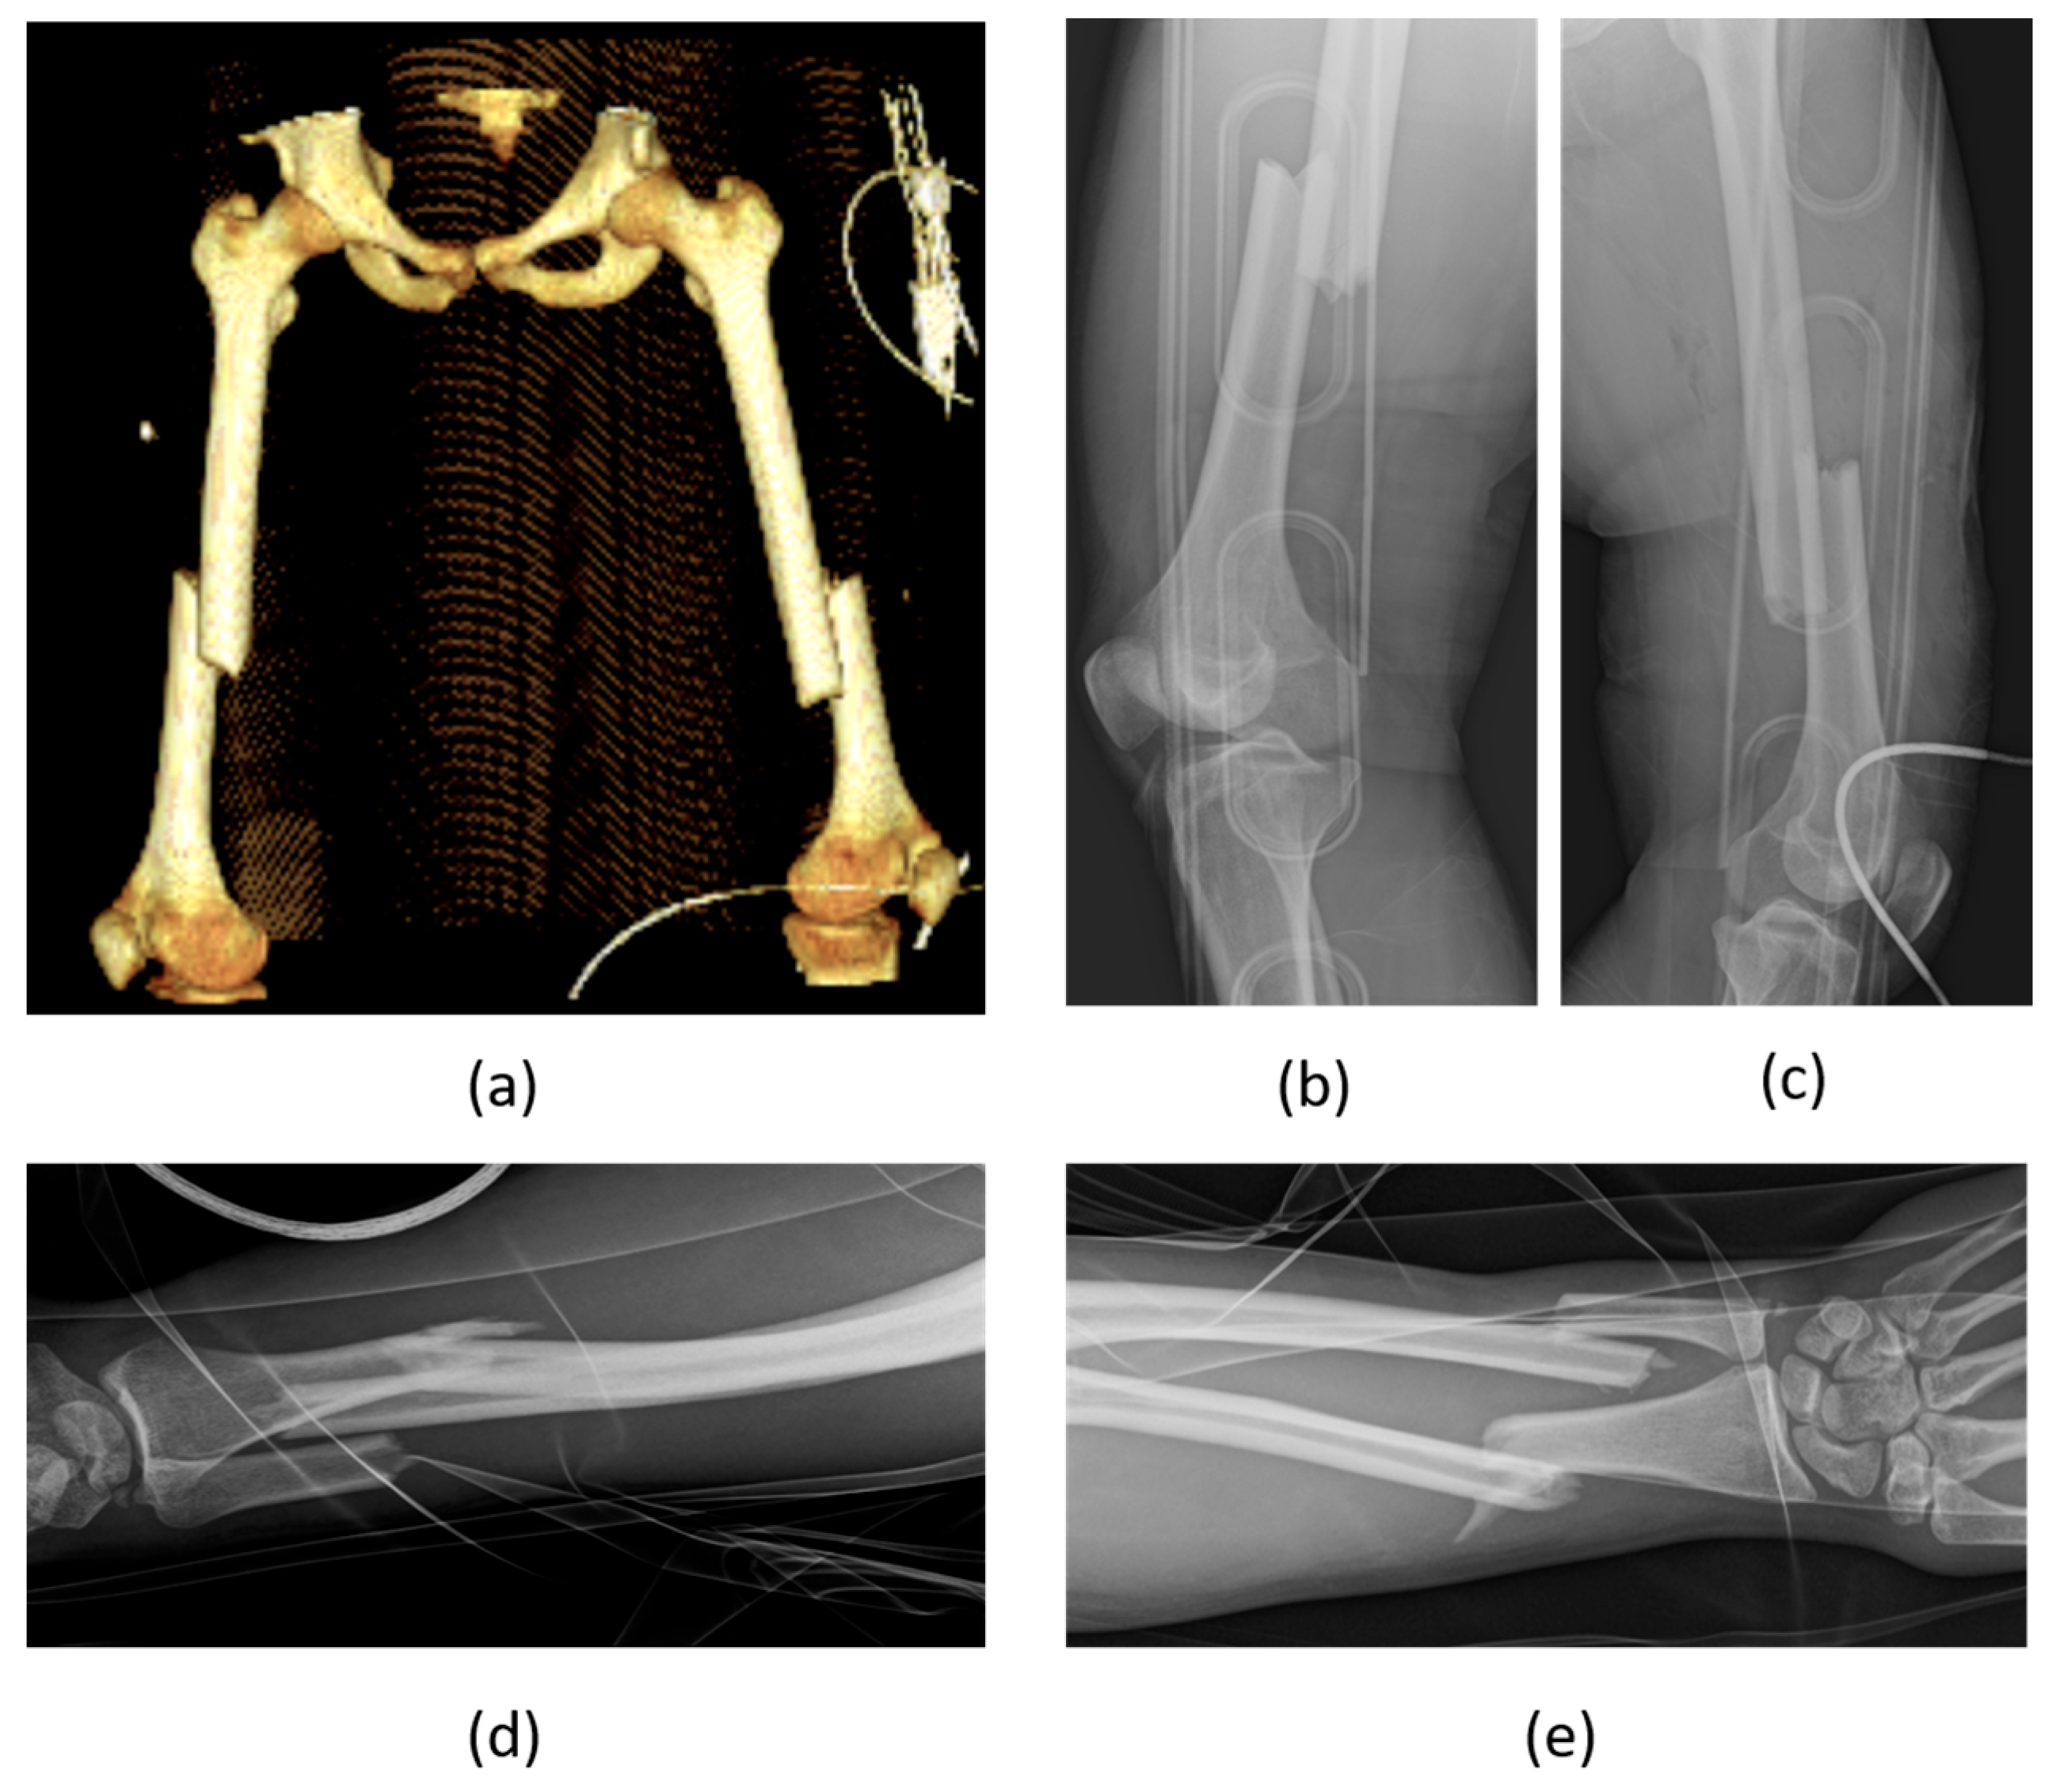

A recently published, retrospective analysis of 16,359 cases from the “German Trauma Registry” [48] confirmed the “morbidity–mortality paradox” in the orthopedic setting. Women were found to be more commonly affected by pelvic fractures than men (with an incidence of 38.4/100,000 versus 33.4/100,000 among men). Of note, when categorizing the population into three age groups (young: under 35 years, middle-aged: 35–65 years, and elderly: over 65 years), it was observed that men were more prevalent in the younger two categories (Figure 3), while women were more common in the elderly group. Across these age groups, men reported a higher incidence of acetabular fractures, whereas women exhibited a higher incidence of unstable pelvic girdle fractures. Men also showed a higher rate of fractures caused by polytrauma. Furthermore, rates of surgery, morbidity, and mortality related to these injuries were higher in men compared to women.

Similarly to hip and pelvic fractures, also proximal humerus fractures, which account for 4–5% of all fractures, as well as other fragility fractures, are more commonly reported in the elderly female population, even if the mortality rate is consistently found to be higher in the male population [49].

Orthopedic surgeons can play a pivotal role in detecting victims of domestic violence through the identification of victim profiles and risk factors associated with such violence. Perpetrators are often intimate partners, including spouses or former spouses. Key risk factors for domestic violence include being a young adult woman, often belonging to visibly racialized communities and/or to lower socioeconomic strata, and being in short-term relationships. Injuries to the head and neck were the most common, with over a third of victims attributing their injuries to falls. Musculoskeletal injuries, noted in as many as 42% of cases, frequently involve the upper limbs and the torso. These injuries represent the primary cause of death among women aged 1 to 34 years [102].